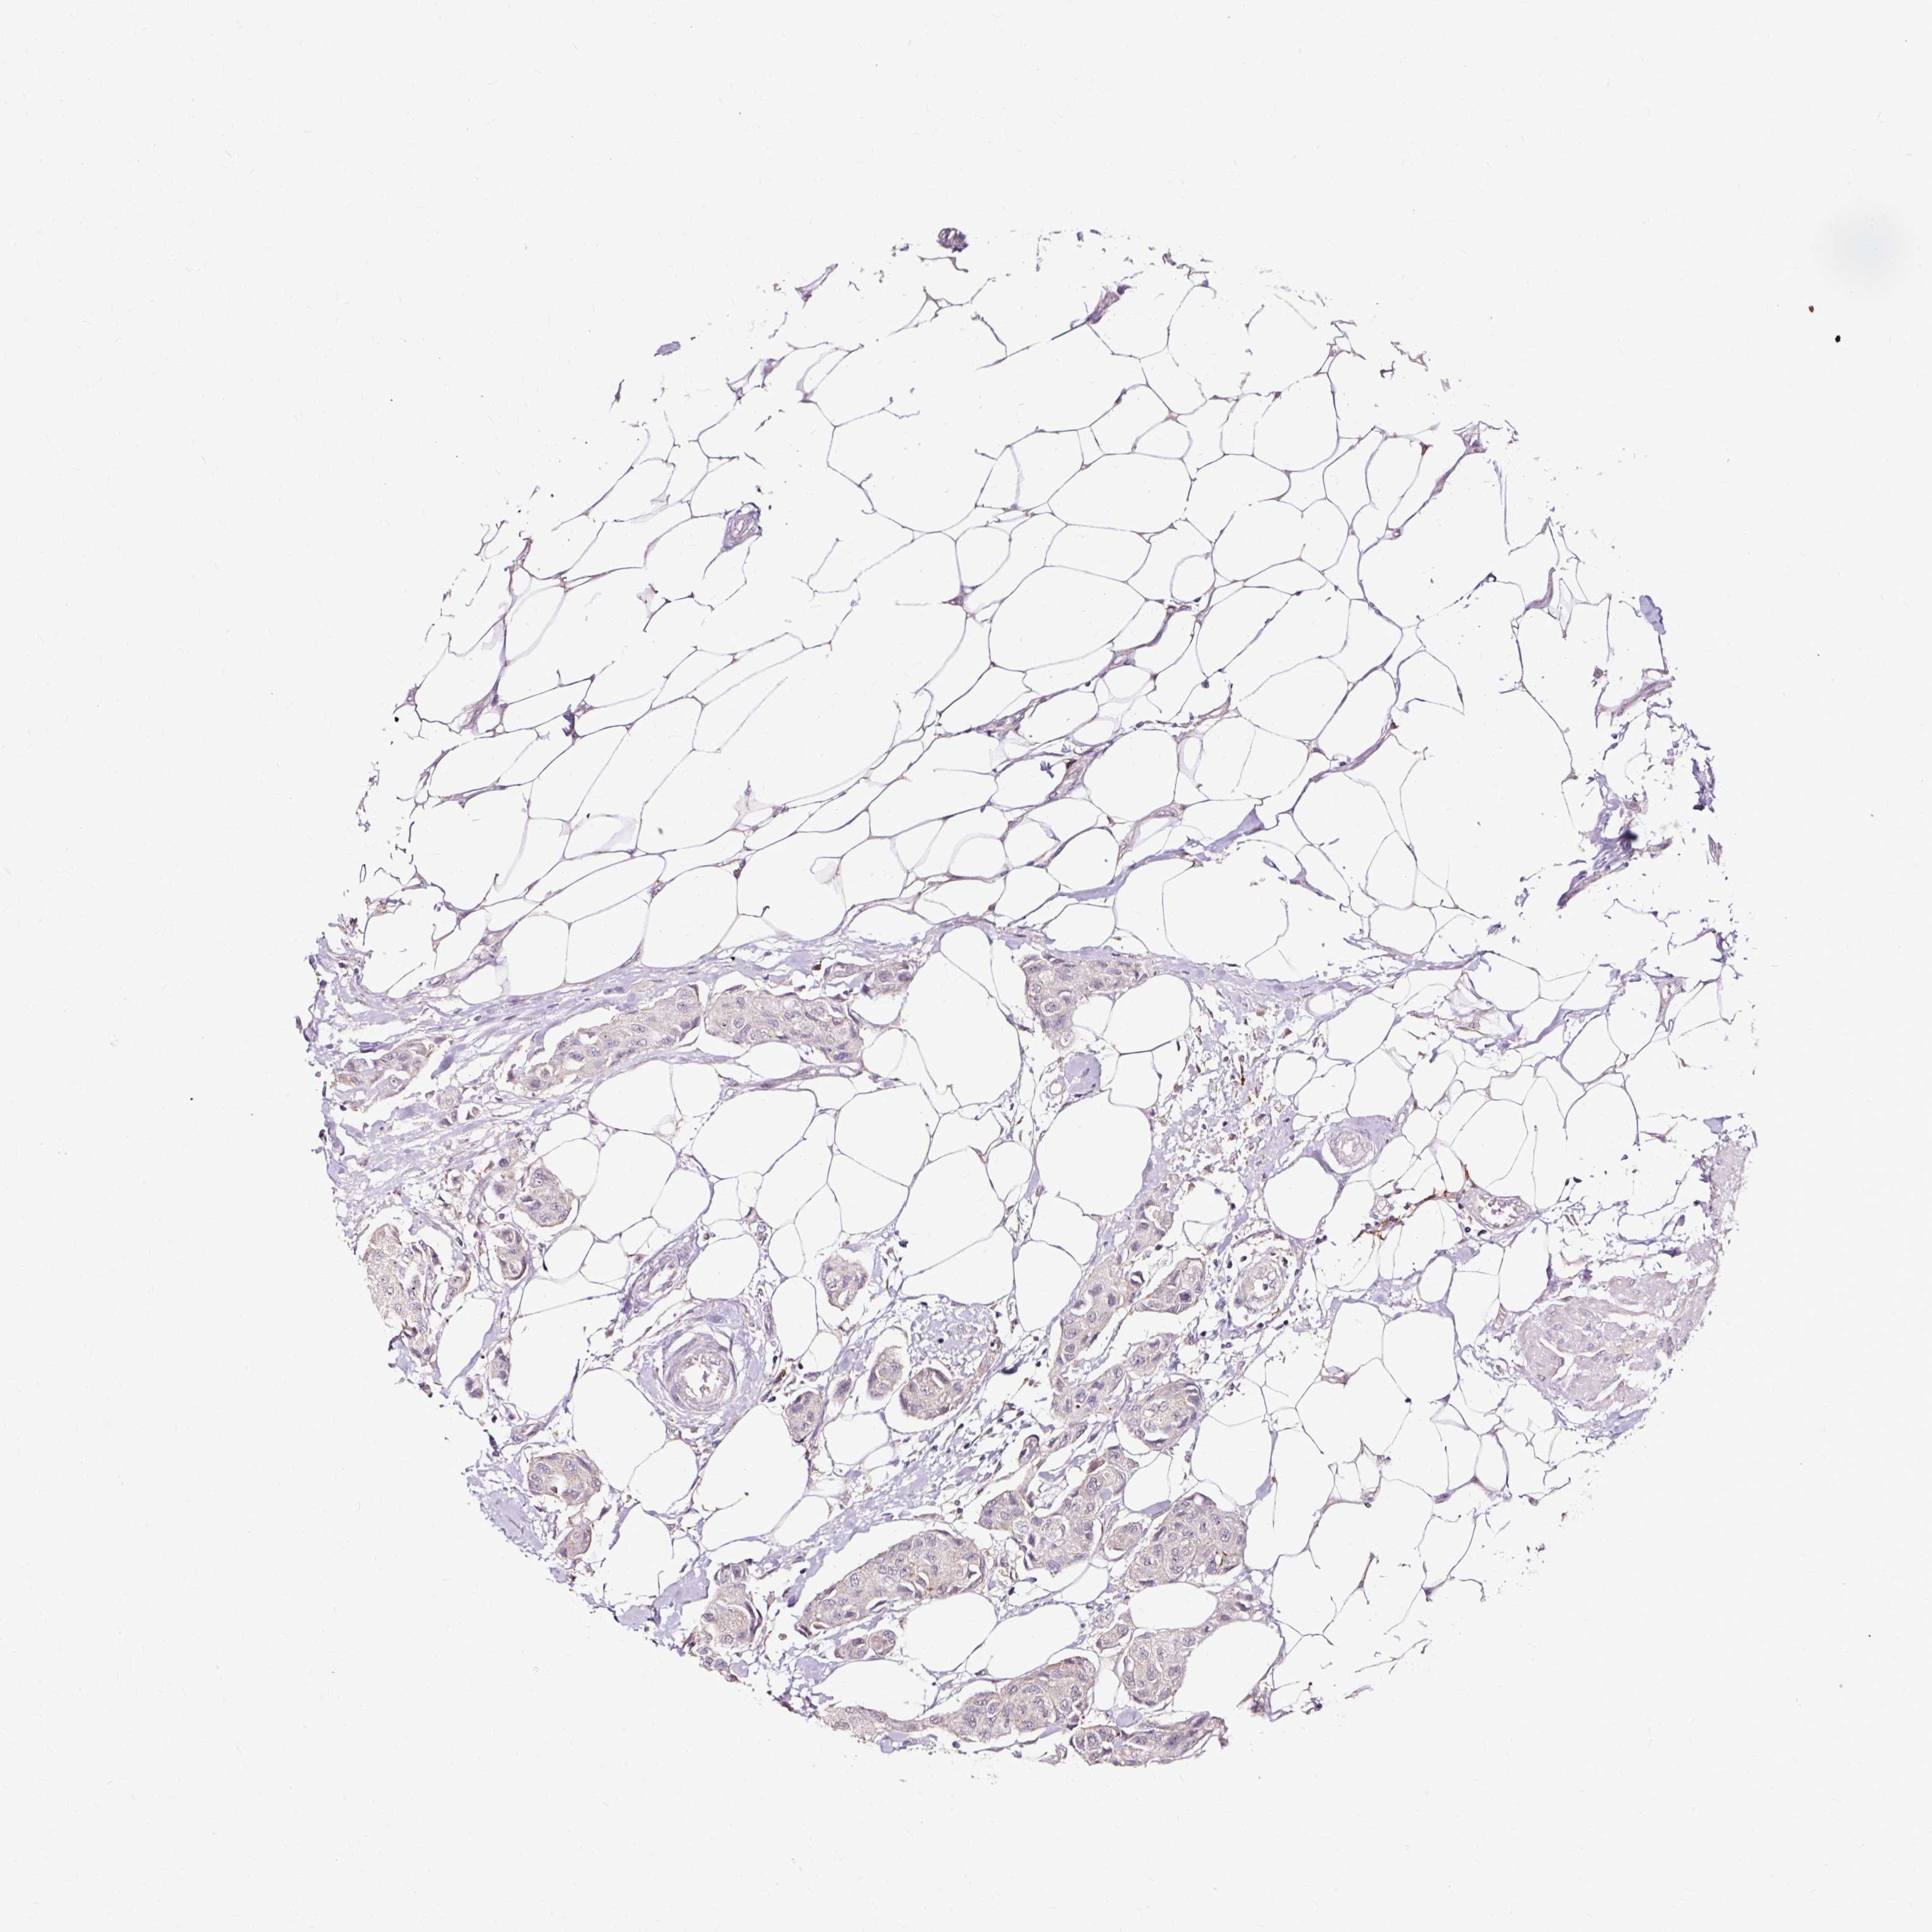

CANCER BREAST CANCER Show tissue menu

BRCA TCGA BRCA VALIDATION PROTEIN EXPRESSION

ANTIBODIES

AND

VALIDATION